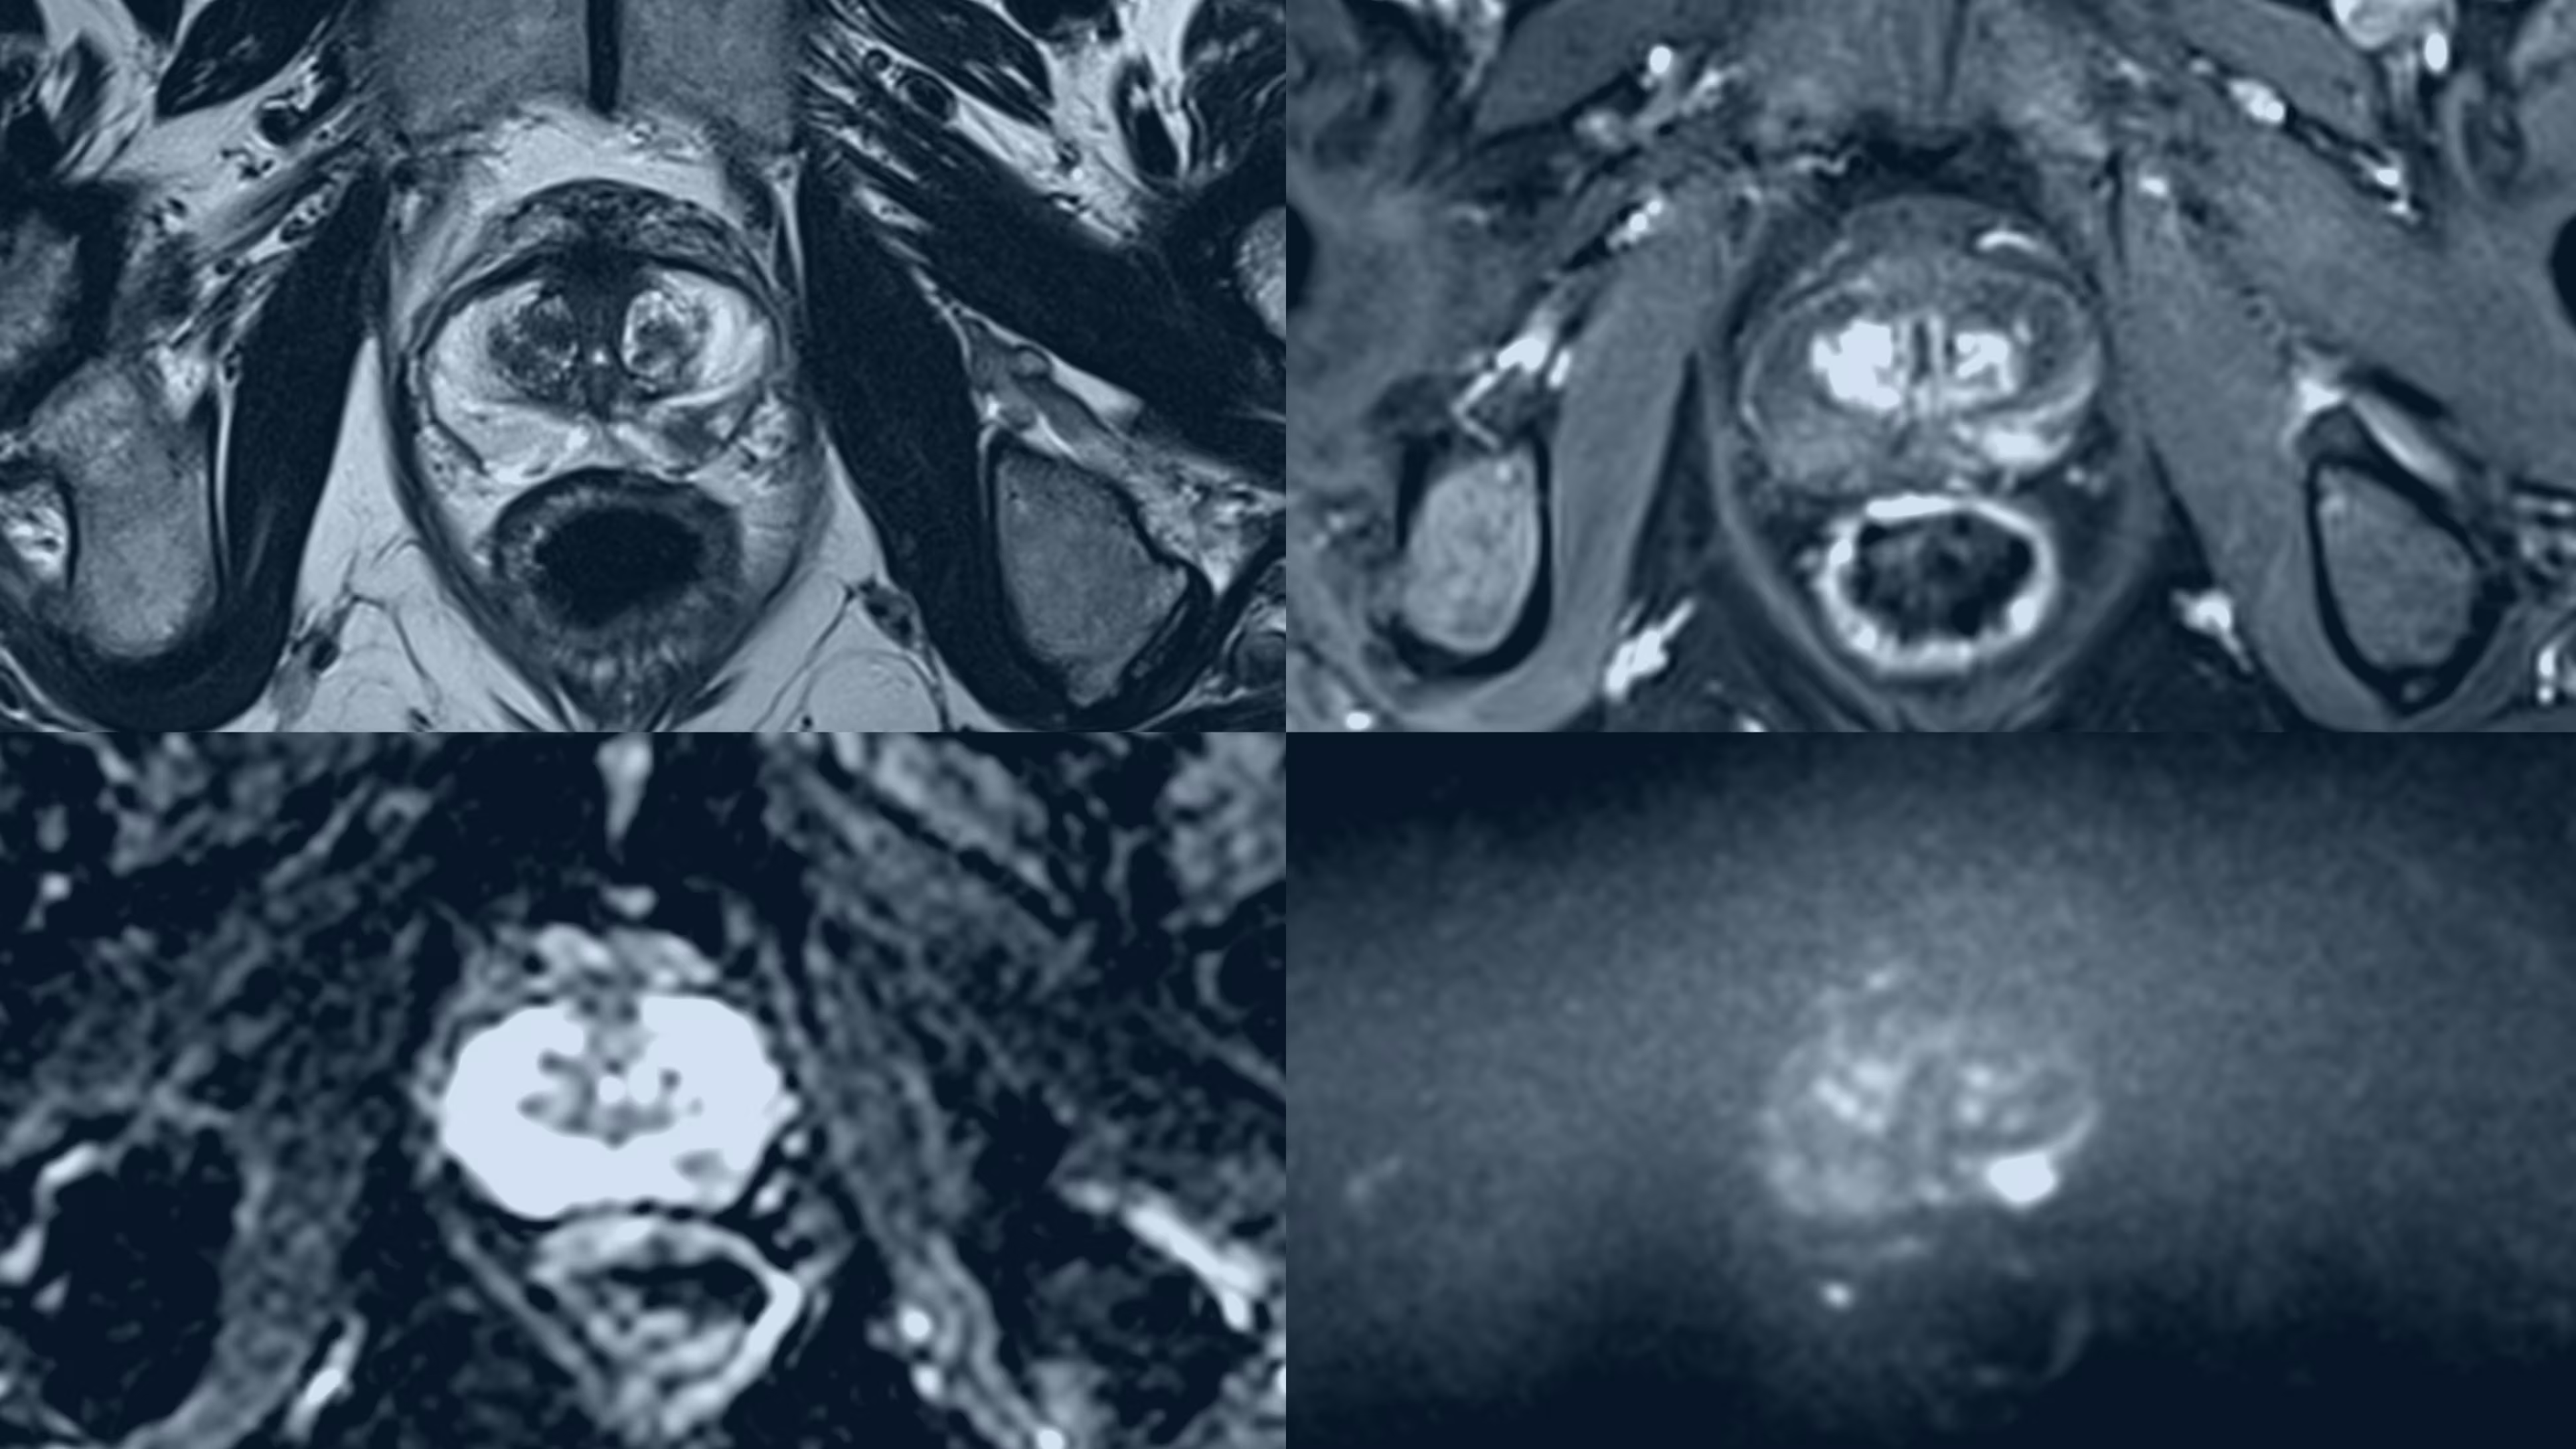

A recent study shows that prostate cancers can be detected using shorter, more affordable scans, potentially improving early diagnosis and reducing healthcare costs.